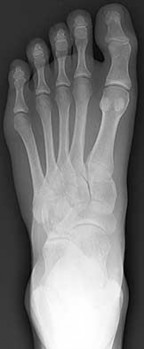

Question 10:

A 30-year-old female sustains a midfoot injury after falling from a horse. Radiographs demonstrate diastasis between the bases of the 1st and 2nd metatarsals. In a normal anatomic state, the native Lisfranc ligament originates and inserts on which two bony structures?

Correct Answer: Lateral aspect of the medial cuneiform to the medial aspect of the base of the 2nd metatarsal

Explanation:

The Lisfranc ligament is a stout, obliquely oriented intra-articular ligament that acts as the primary stabilizer of the second tarsometatarsal joint complex. It connects the lateral aspect of the medial cuneiform to the medial aspect of the base of the second metatarsal. Importantly, there is no direct ligamentous connection between the bases of the first and second metatarsals.